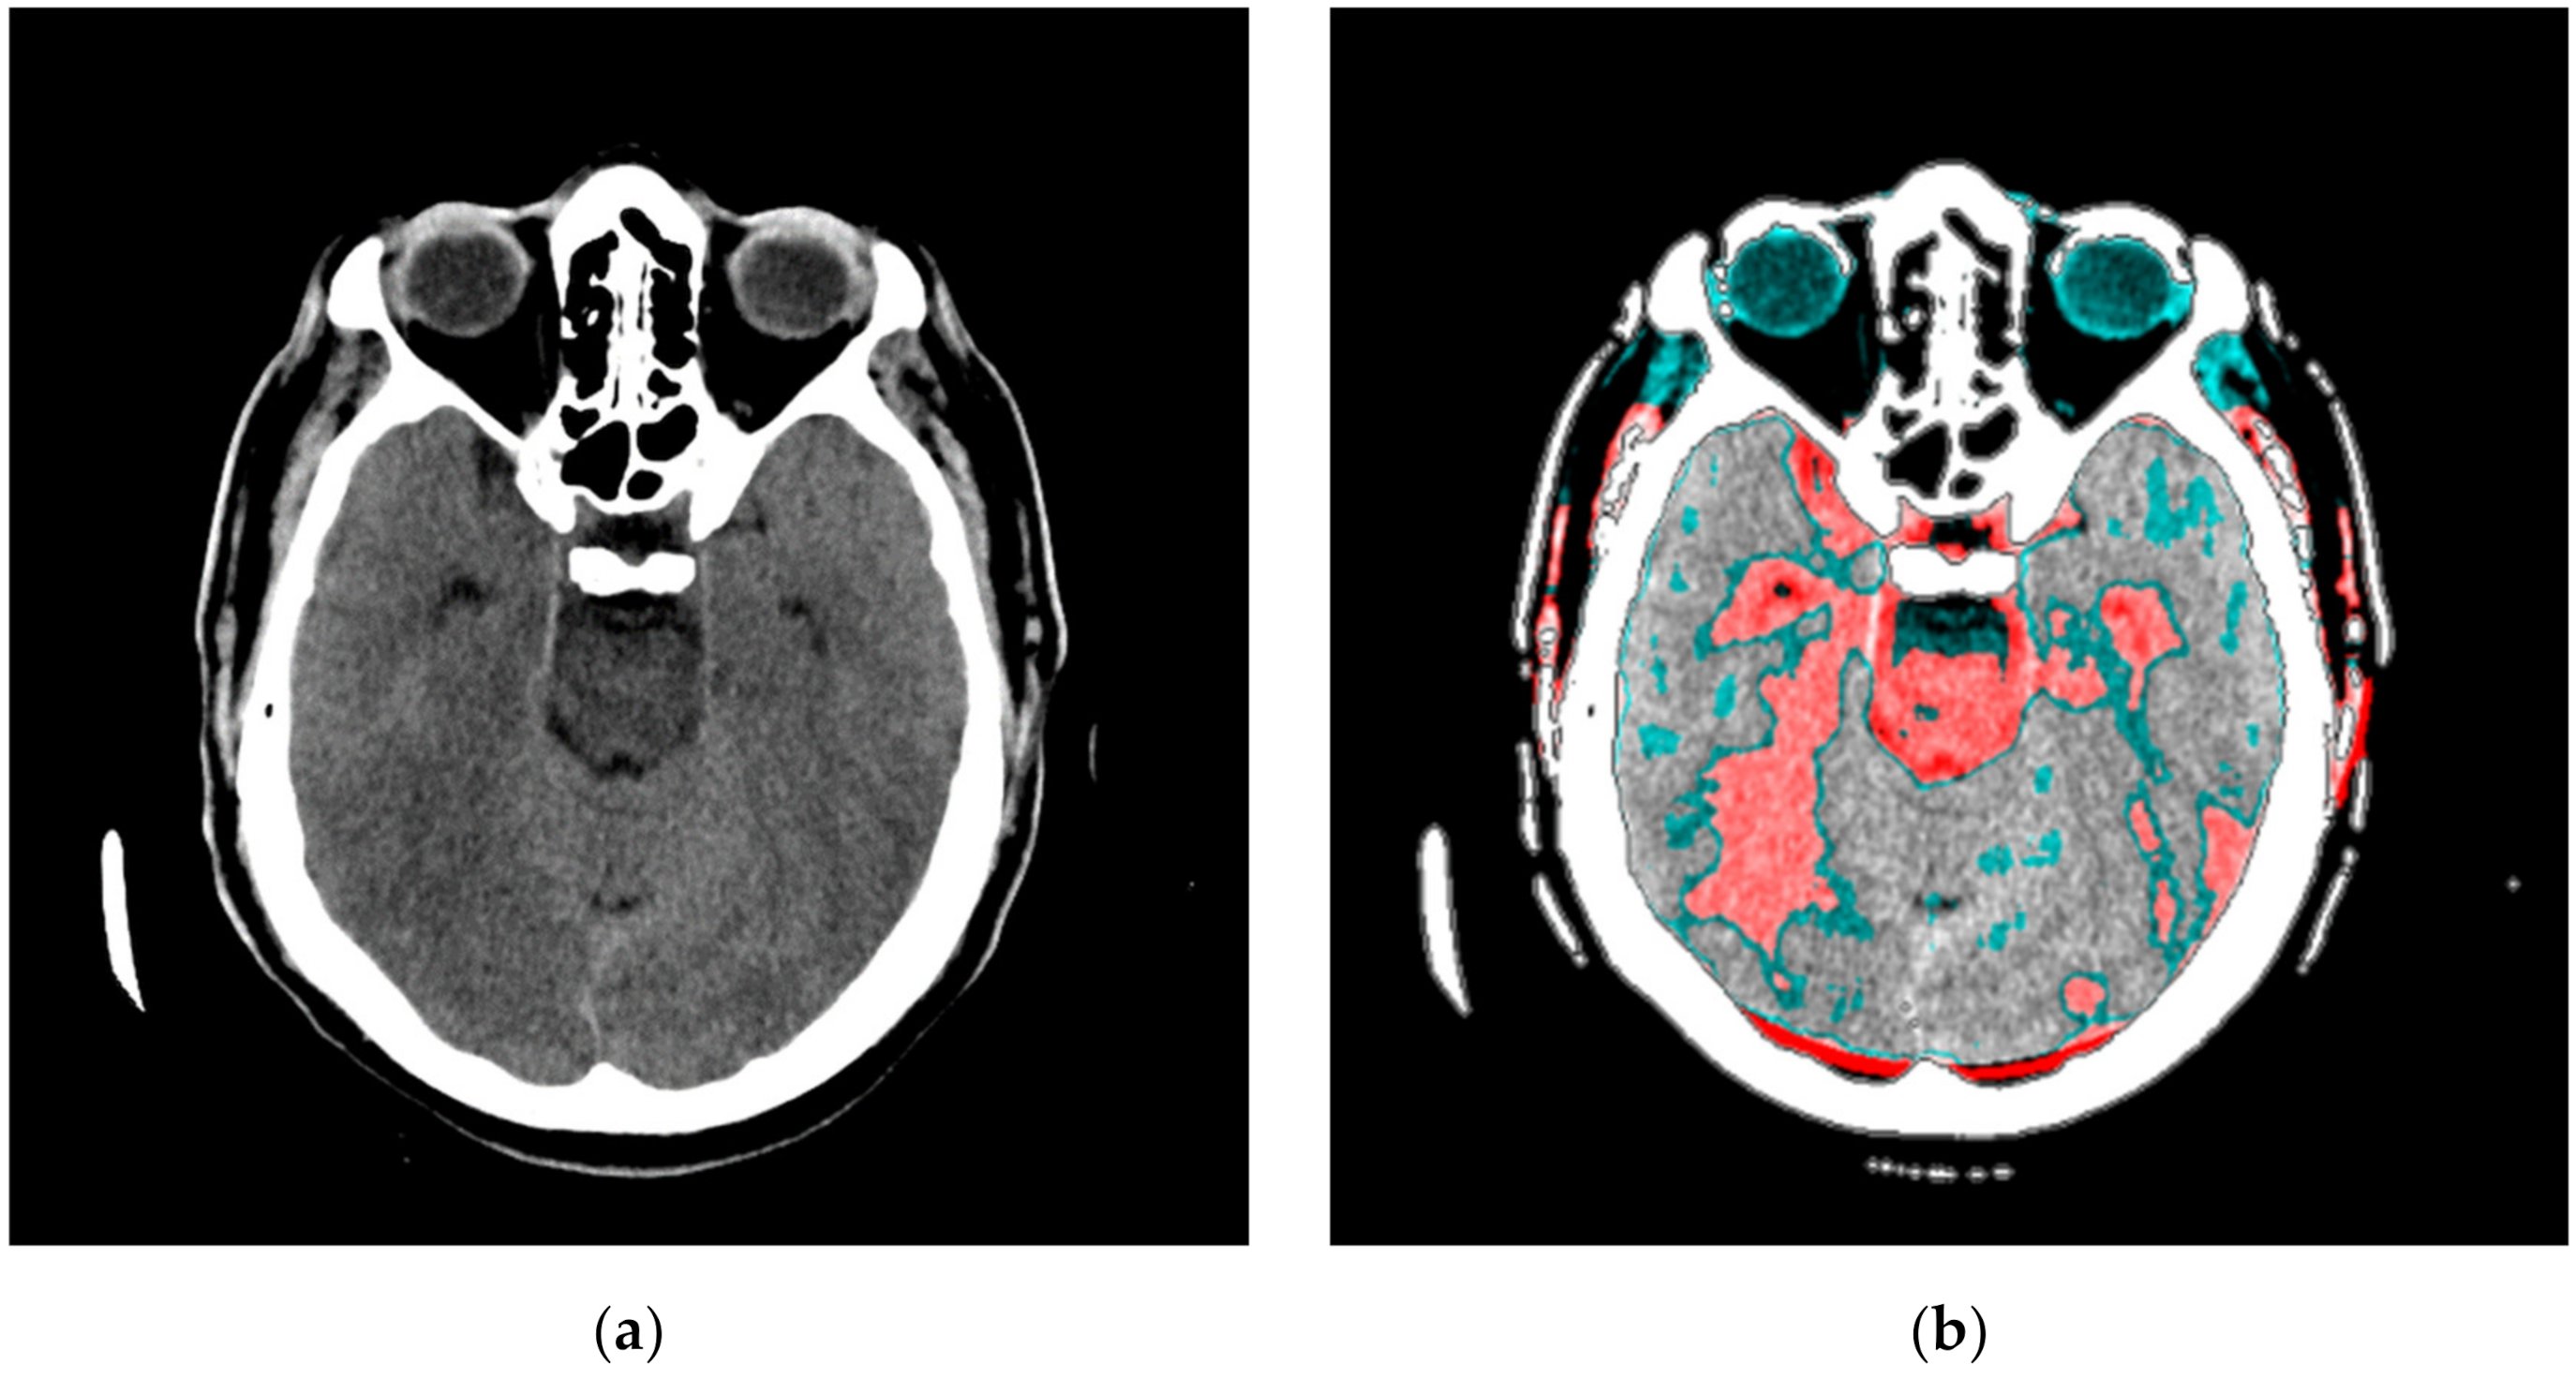

In our research approach, in marking content and regions of interest all values that do not contribute to the content are set to a pixel value of zero. In this way, the levels of black (which have a value of zero or slightly greater than zero), white values (which have a maximum value), and values of gray that are not contained in the central part of the gray are set to zero so as not to interfere with the physician conclusion while observing the central segment. At the same time, white parts (for example, bones) do not affect the mean value of the observed part. The smart visualization and the summary of the system output of the developed SVMI model is shown in Figure 3.

Figure 3.

Summary of the system outputs.

After determining the localization of the appropriate level of a particular cross-section by an experienced neuroradiologist, centering and masking of contents and regions of interest are performed. For a non-contrast MDCT scan in a DICOM-standardized format file, in which integers represent all pixels, it is necessary to extract useful information. Therefore, only the gray range is observed so that all gray values are less than a particular value, all values greater than the other selected value are observed, and all are set to zero so as not to affect the mean value of the selected segment. Adjacent pixel values are colorized differently, meaning that physicians do not need to recognize close levels of gray because segments that have similar pixel values are different. By masking this content, a specific part can be selected (above, below, left and right 1/3, or 2/3 vertically and horizontally) so that only the part of interest is magnified. On the right, relative values of gray from zero to one are provided with a label that shows the color. The minimum and maximum values are chosen arbitrarily so that only the range of gray is observed. All other values are zero and do not affect the mean and standard deviation. Assigned colors can be changed according to the physician’s preferences to provide a clearer view of image segments with the same pixel value. The mean and variance are calculated for the selected range. It is also possible to perform averaging so that the close ranges are more clearly separated from the rest of the pixels.